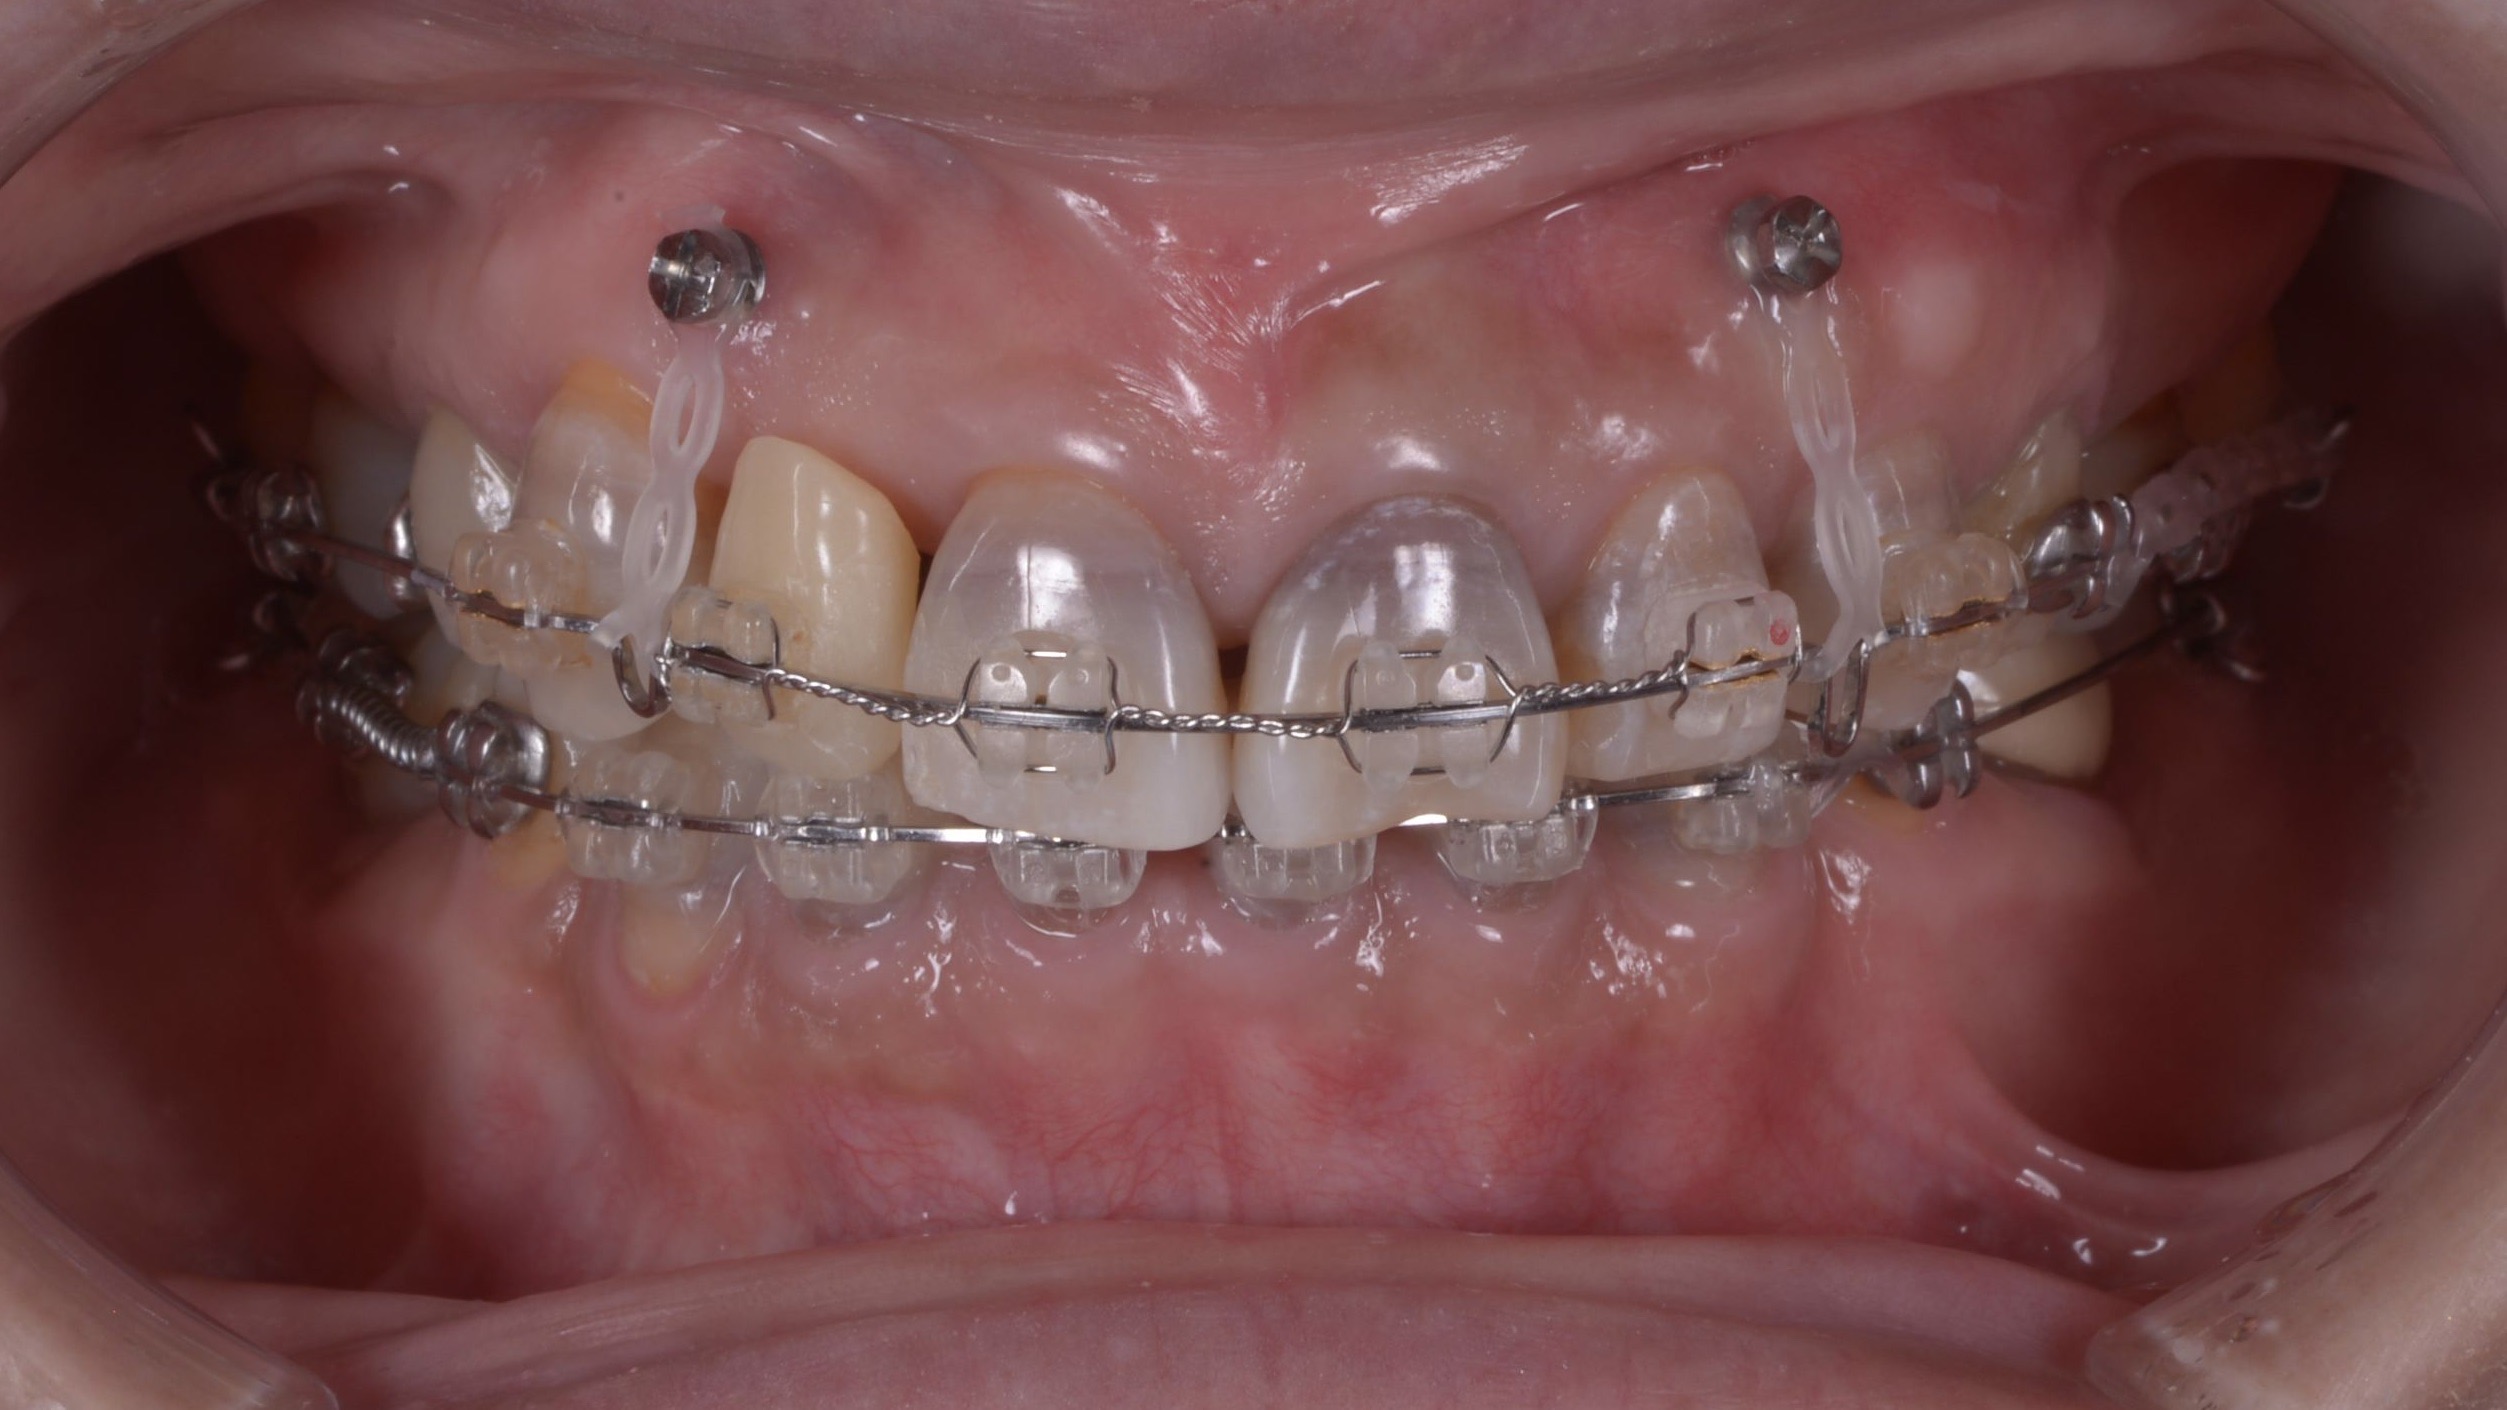

類に漏れず矯正治療によってインプラント本数の削減のみならず、ご自身の歯で欠損部のスペースクローズを行い、最も重要な前歯の正常な噛み合わせとすり減り変色歯の改善をセラミックを接着着せ替えすることで達成する計画を立案しました。

すり減った分は歯は生えてきます。矯正治療で元の位置まで引き戻します。その結果セラミッククラウンを入れる前では前歯同士が噛み合いません、でもそれで良いのです。

矯正治療終了時に歯の長さを先ずはプラスティックをすり減った先端部分に盛り足して、本来の歯冠形態を回復し、お顔や下唇と調和しているか確認を患者と共に行います!